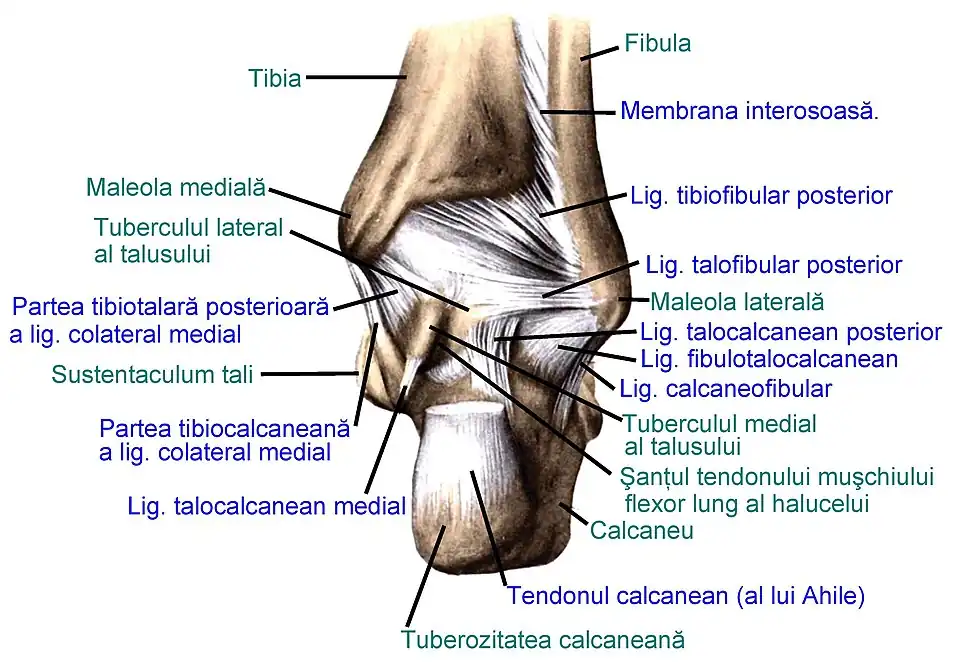

Ligamentele articulațiilor piciorului drept, văzute lateral (după Sobotta's Atlas and Text-book of Human Anatomy 1909)

Ligamentele articulațiilor piciorului drept, văzute medial (după Sobotta's Atlas and Text-book of Human Anatomy 1909)

Ligamentele articulațiilor piciorului drept, văzute posterior (după Sobotta's Atlas and Text-book of Human Anatomy 1909)